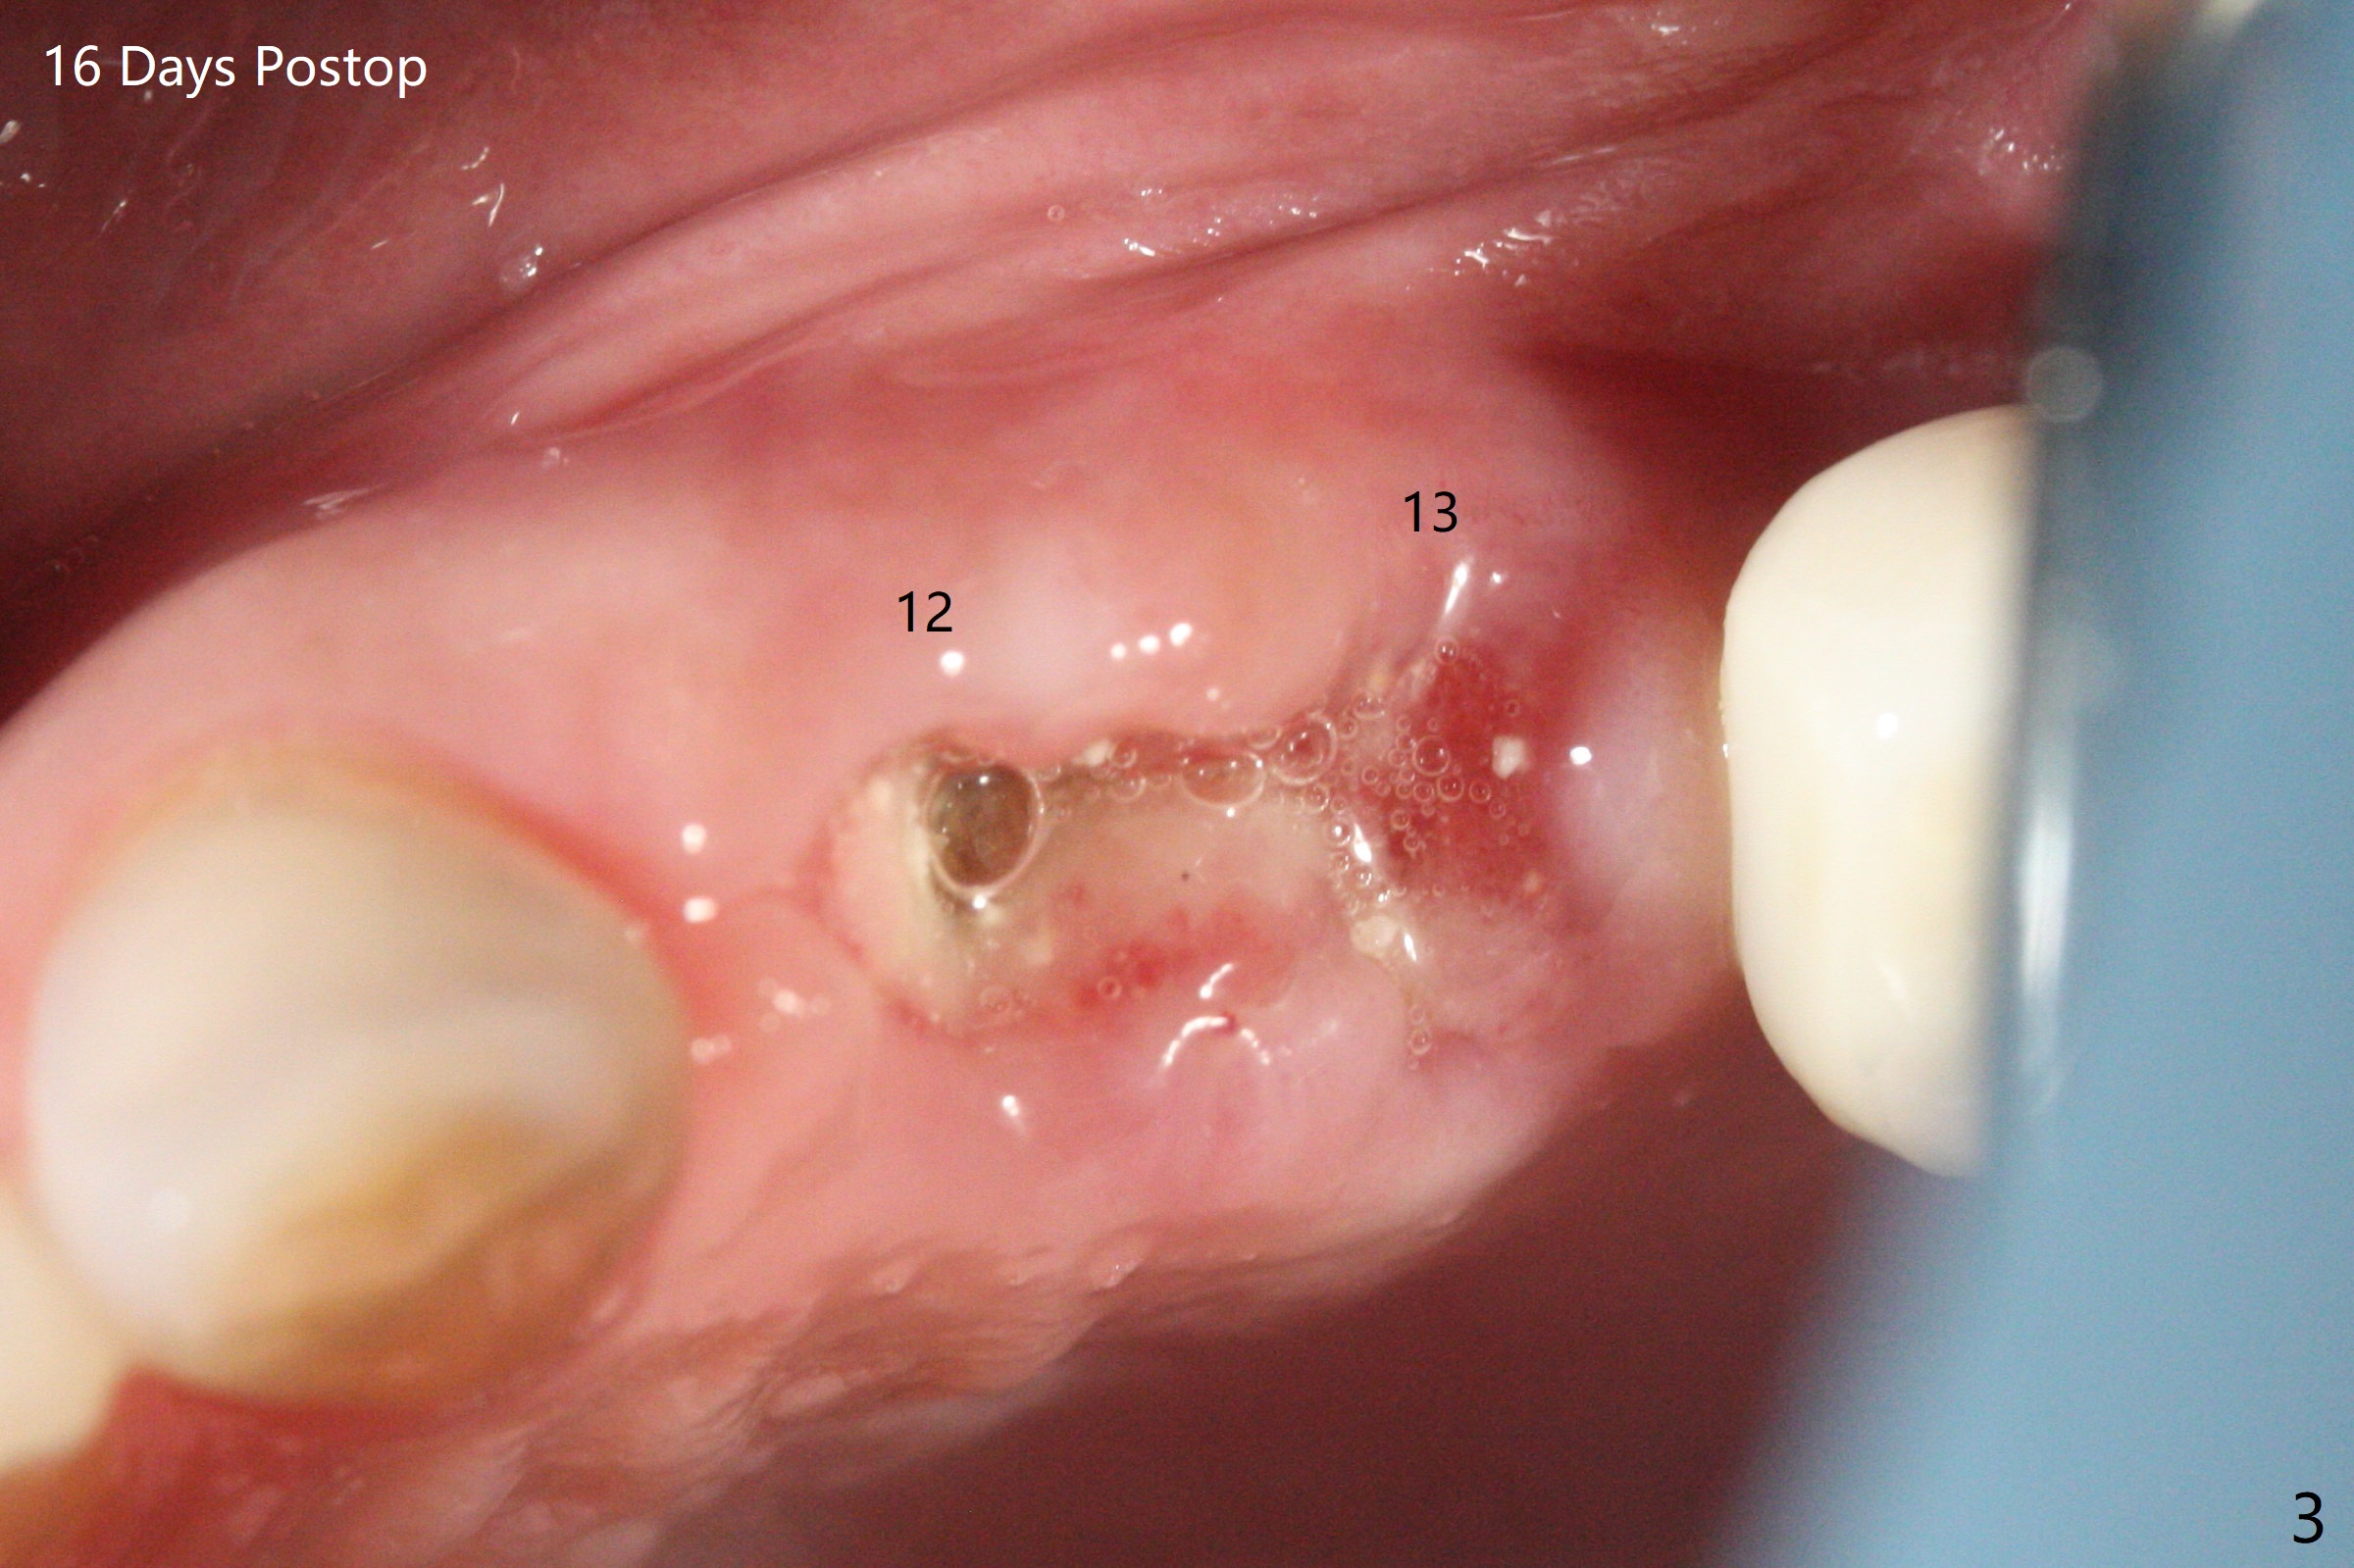

42岁女,12号牙断裂(图一),在拔除中不幸损伤13号牙,一起拔除,用GEM21S与异体骨和人工骨进行位点保存,术后骨粉一直脱落,病人觉得伤口有臭味。术后16天根尖片显示骨粉仍在牙槽窝(图二),伤口尚未愈合(图三),骨粉密度不高(图四,五)。讨论后,决定去除余留骨粉,重新刮拔牙槽窝,反复冲洗,最好放置粘性骨粉(图六),覆盖PRF和不可吸收膜,使用PTFE缝线,树脂敷料。术后三周膜和骨粉仍在原位(图七,八)。为了恢复龈乳头,术后四,五个月,利用导板去除两个牙位牙槽嵴骨质(图九),把植体植入牙槽嵴深部,之间便形成突起的牙槽嵴(图十:C)以及龈乳头。植牙整合后,利用临时牙冠,反复调整,挤压形成比较正常龈乳头。